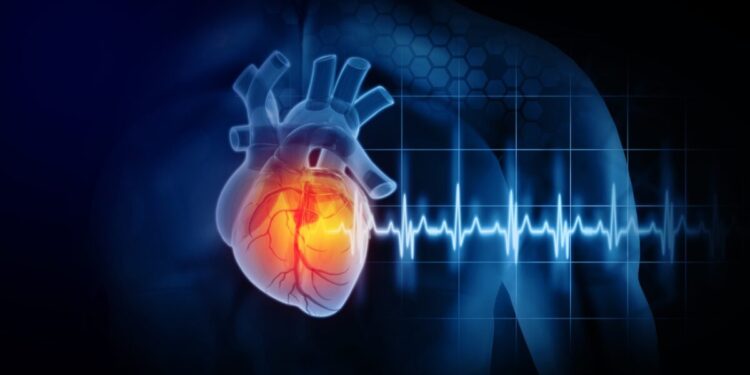

Η Ελλάδα έχει αναδειχθεί ως πρωτοπόρος στην πρόληψη καρδιαγγειακών νοσημάτων μέσω του Εθνικού Προγράμματος Πρόληψης “ΠΡΟΛΑΜΒΑΝΩ”. Η αναπληρώτρια υπουργός Υγείας, Ειρήνη Αγαπηδάκη, παρουσίασε την εμπειρία της σε ειδική εκδήλωση για την πρόληψη των καρδιαγγειακών παθήσεων.

Το πρόγραμμα αποτελεί τη μεγαλύτερη επένδυση Δημόσιας Υγείας στην Ελλάδα των τελευταίων 40 ετών, σύμφωνα με την υπουργό. Πάνω από 1,8 εκατομμύριο πολίτες έχουν πραγματοποιήσει αιματολογικές εξετάσεις και χιλιάδες έχουν παραπέμφθεί για ελέγχους στεφανιαίας νόσου και ισχαιμίας.

Η Ελλάδα δείχνει τον δρόμο προς την πρόληψη των καρδιαγγειακών νοσημάτων, με την εφαρμογή ενός φιλόδοξου προγράμματος που ήδη σώζει ζωές. Η πολιτική βούληση και η επιστημονική πρακτική αποτελούν βασικούς παράγοντες για την επιτυχία του προγράμματος.

Η Ελλάδα προτείνει ένα ισχυρό ευρωπαϊκό πλαίσιο για την πρόληψη των καρδιαγγειακών νοσημάτων, με στόχο τη μείωση των πρόωρων θανάτων σε ολόκληρη την ΕΕ. Η πρόληψη γίνεται ολοένα και πιο σημαντική στην καθημερινότητα των πολιτών, αλλάζοντας την κουλτούρα στα θέματα υγείας.

Η Ευρωπαϊκή Επιτροπή και άλλα κράτη-μέλη έχουν εκφράσει το ενδιαφέρον τους για το πρόγραμμα πρόληψης των καρδιαγγειακών νοσημάτων της Ελλάδας, αναγνωρίζοντας την επιτυχία του. Η Ελλάδα αποτελεί πρότυπο για την ανάπτυξη ολοκληρωμένων προγραμμάτων πρόληψης στην Ευρώπη.